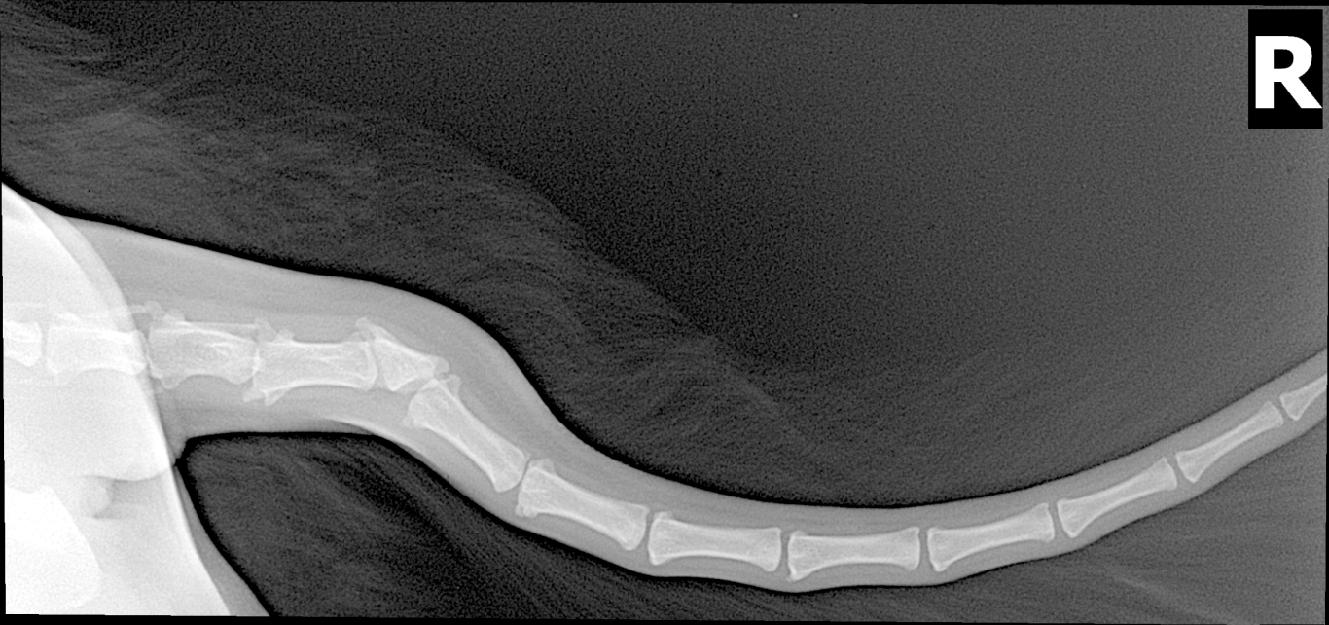

Dobrý den. Pokud rtg snímek patří Vašmu psu (v dotazu není zmíněno), můžete na něm vidět odpověď na svůj dotaz. Je o tzv. zálom, čili špatně vyvinutý ocasní obratel. Označuje se jako klínový obratel. V daném místě je ocas špatně pohyblivý, inervace je atypická, takže jakákoliv manipulace je bolestivá. Většinou se doporučuje podobně deformovaný ocásek amputovat už v prvních dnech života štěněte, aby se zabránilo přesně těm potížím, které teď řešíte. Rada je těžká. Pes za bolesti nemůže. Řešení je stříhat nebo vyčesávat velice opatrně, případně v sedaci, krajním řešením je pak provedení amputace v místě lomu. S pozdravem, Jan Havránek